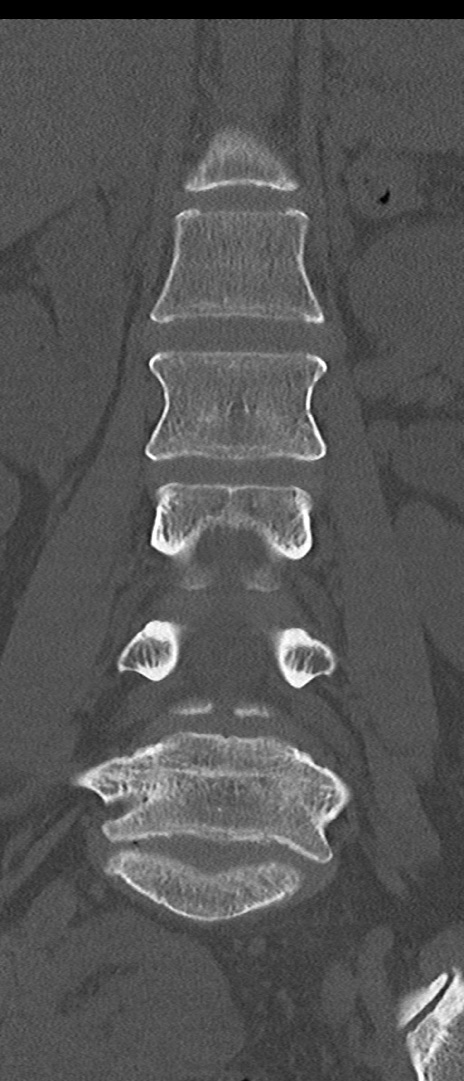

【整形】TIPS症例4 腰椎CT(冠状断像)

腰椎CT